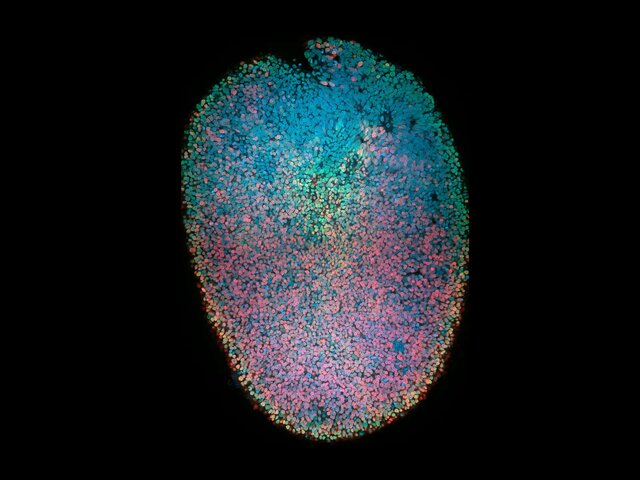

علم ارگانوئید شامل کشت نسخههای مصنوعی کوچک از اندامهای داخلی فرد برای تحقیقات بر روی داروها و بیماریها میشود. این ارگانوئید از نخاع انسان، تفکیک جوامع سلولی را نشان میدهد که به نورونها و نورونهای حرکتی تبدیل میشوند.

تصویر از: شان موریسون(Sean Morrison)